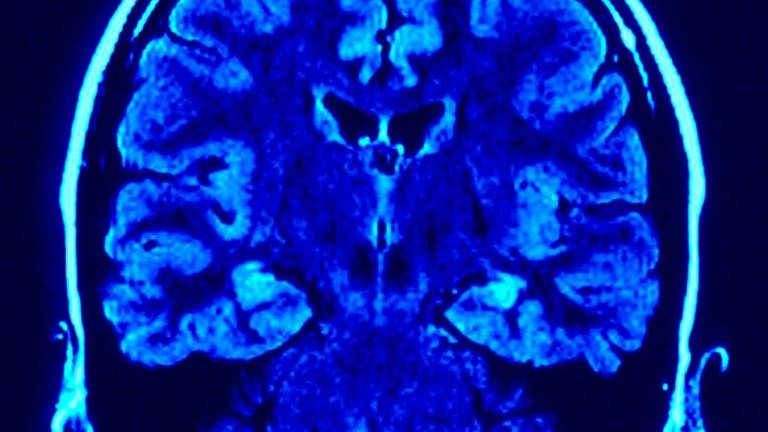

La estimulación intracraneal es un procedimiento quirúrgico por el que se implantan una serie de electrodos en el cerebro que liberan impulsos eléctricos para reducir la activación anormal de regiones cerebrales en pacientes con Parkinson.

Tras el estudio descubrieron que el modo y el tiempo que las regiones del cerebro utilizan para comunicarse se reduce después de aplicar la estimulación intracraneal, especialmente en las regiones que ejecutan los movimientos corporales.